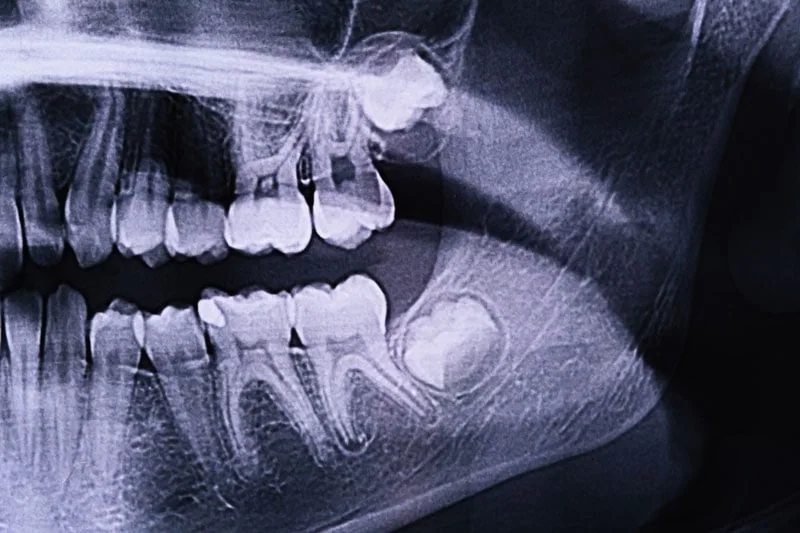

A bölcsességfog eltávolítása előtt természetesen először alaposan megvizsgáljuk a szájüreget: panoráma röntgen készül, valamint szükség esetén 3D CBCT felvétellel gondoskodunk a még pontosabb diagnózisról és a beavatkozás teljes biztonságáról.

A folyamat a bölcsességfog és a szájüreg alapos felmérésével kezdődik. A szájsebész vagy a fogorvos modern röntgendiagnosztikai eljárás során felvételt készít a fogról, hogy felmérje annak pontos helyzetét, illetve a szomszédos foghoz való viszonyát. Ez leggyakrabban panoráma röntgennel történik, azonban bizonyos esetekben kiegészül egy 3D CBCT felvétellel is – ha például nem egyértelmű a fog és az idegek viszonya.